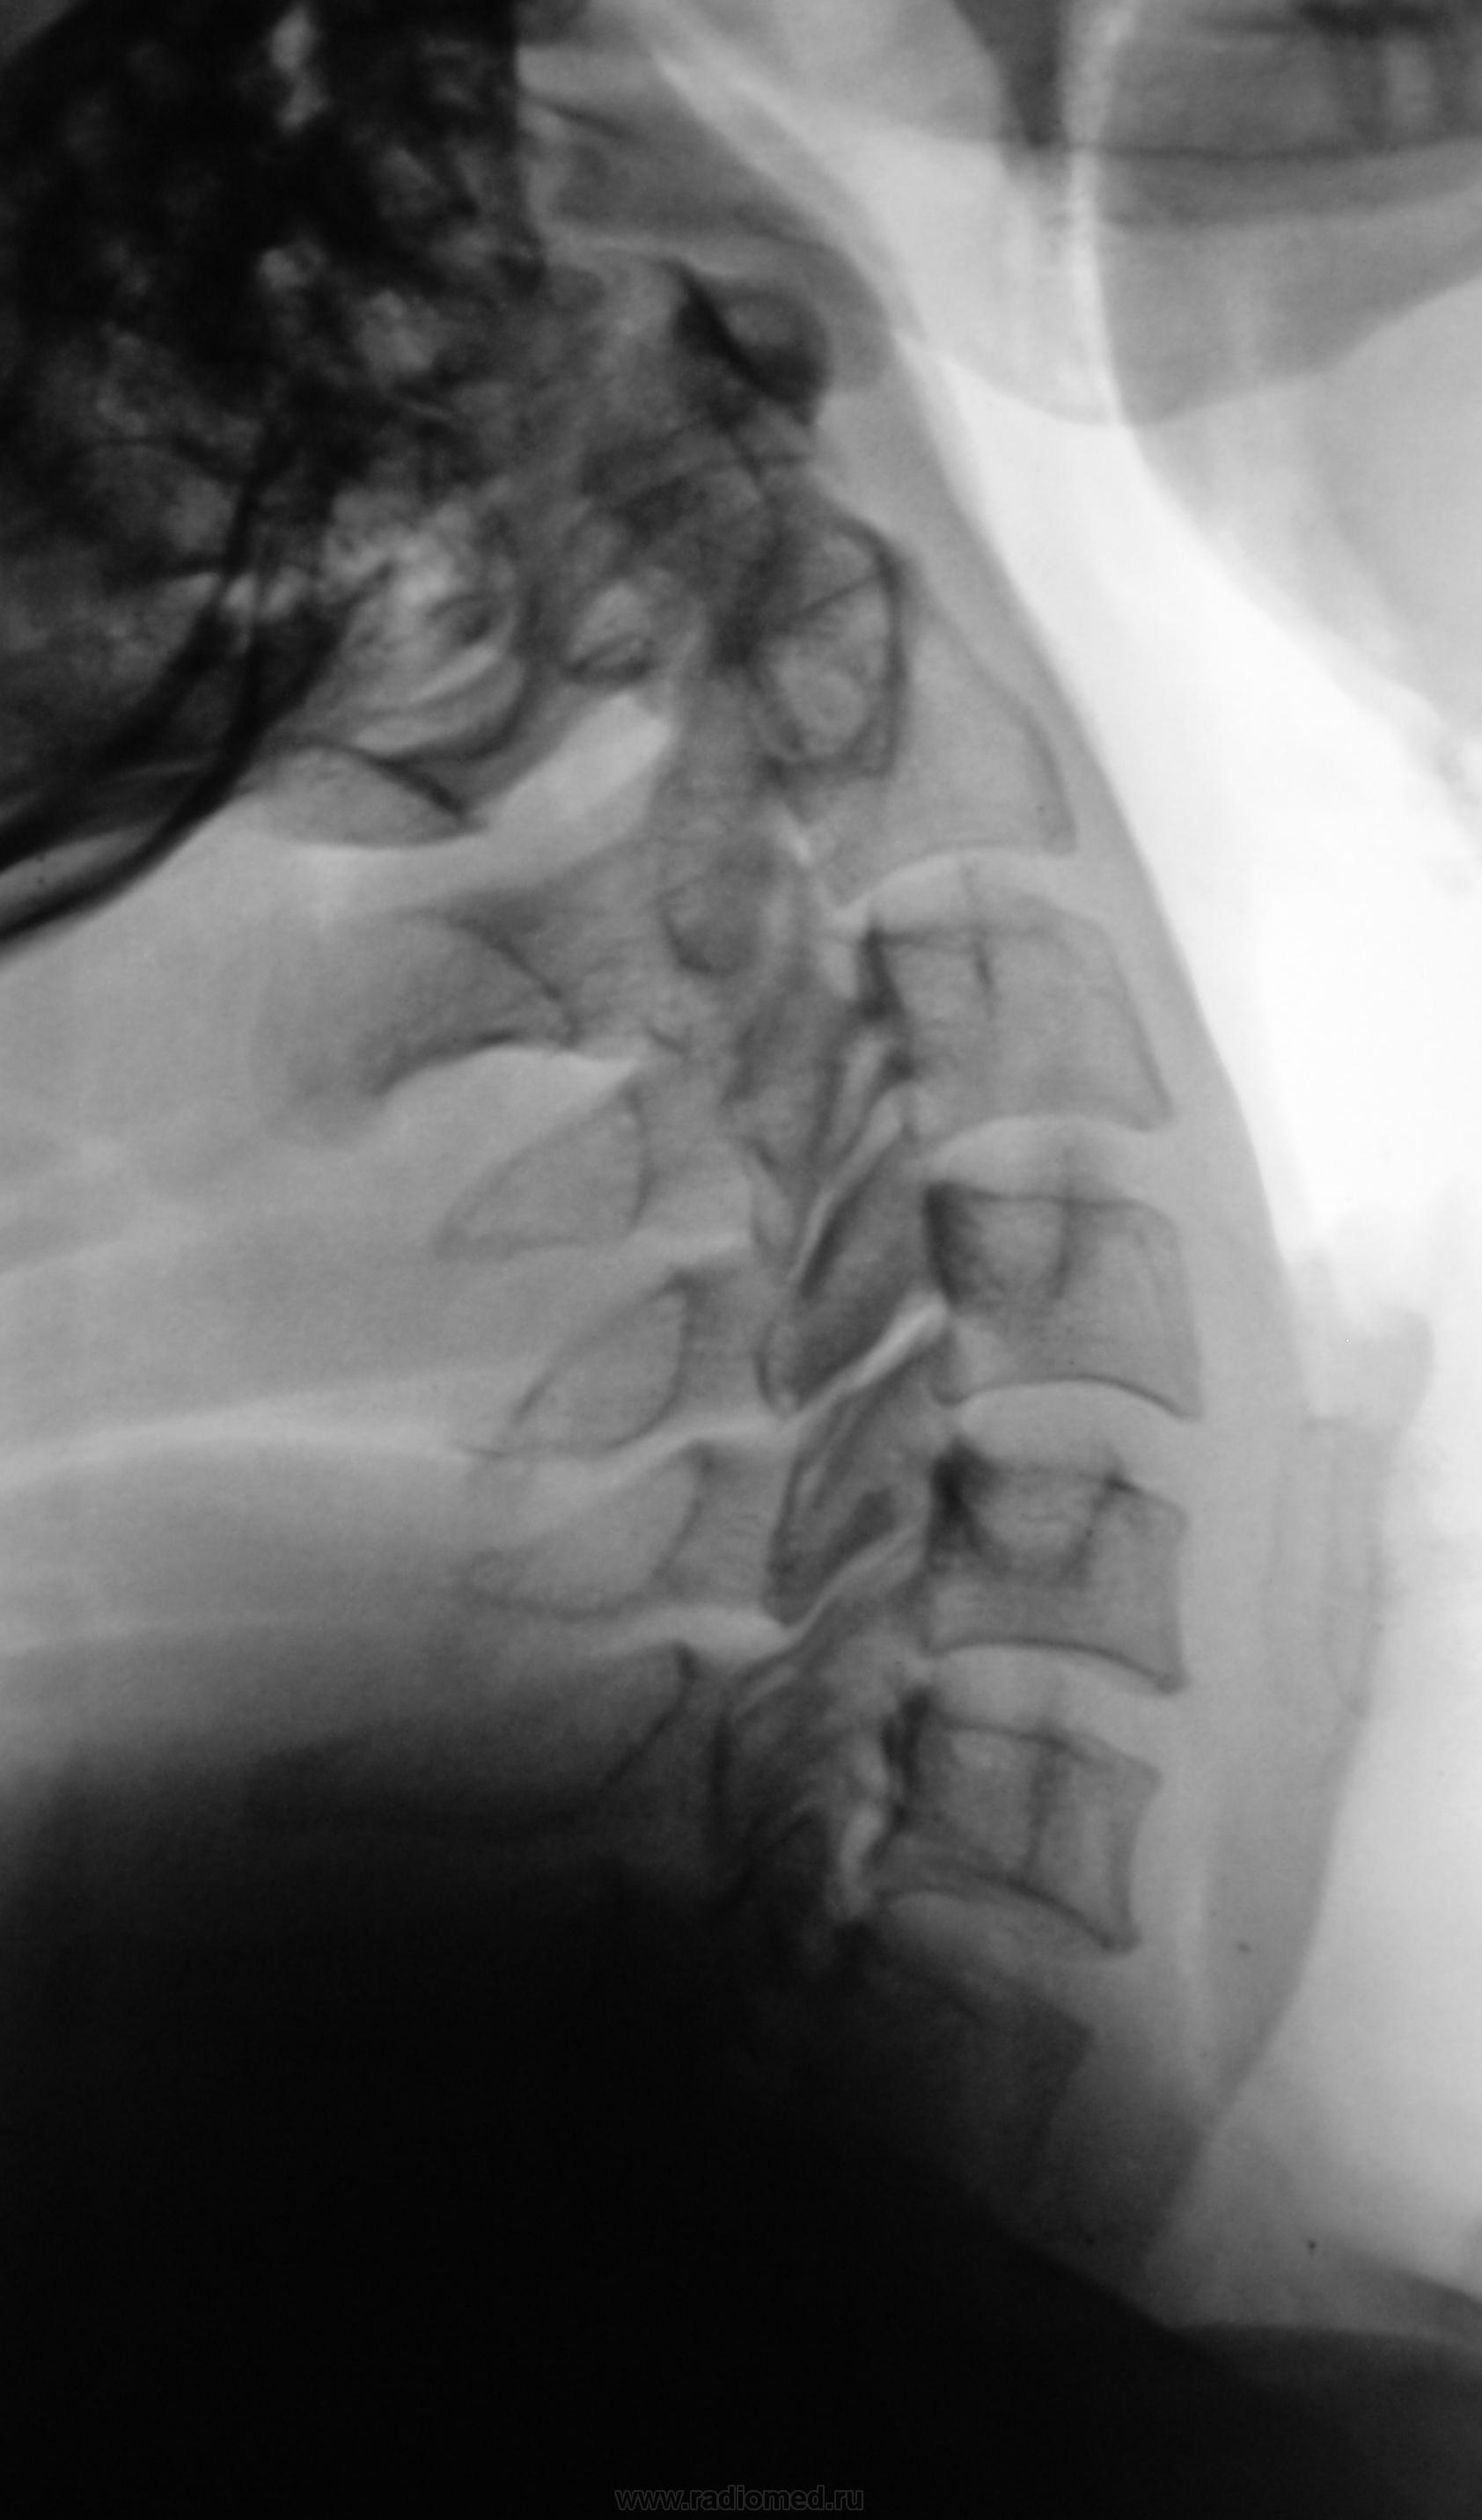

Пациент направлен на функциональную рентгенографию шейного отдела позвоночника.

Похоже на конкресценцию дужек С2-С3.

Да вроде нет. Сращение тел без дуг встречала, а вот сращения дуг без сращения тел нет.

Действительно ни на одном из трёх боковых снимков не видны суставные щели в этом сегменте, что трудно объяснить укладкой.

Не видны, еще не значит, что их нет. Суставы С2-С3 всегда видны хуже нижележащих.

Мне кажется - вот щель сустава.

Согласен с Нелей: щель здесь видна. Но как-то раз или два видел слияние дуг без тел

Не, Валентин Львович, замыкательные пластики везде видны. Проекционное наложение, по-моему мнению.

Я не склонен считать верхнюю замыкательную пластинку Т1 нормальной, кроме этого локальное уплотнение передней продольной связки (не окостенение) от передне-нижнего контура С7, тоже, субъективно у меня в норму не вписывается.

По суставам -щели все.  Явления хондроза от С4 и ниже. Пластинки, помимо уплотнения, дугообразно двояковогнуто пролабируют (хоть и слабо) в тела, как следствие слабости спонгиозного матрикса, возникающего при дегенеративной остеопении в ранних стадиях. Th1 действительно недоступен для адекватной оценки. Предполагается хороший грудной кифоз, вторично обусловливающий передний наклон всего шейного отдела вперед.  Однако, нормой этот позвоночник не назовешь.

Не стал бы в столь мрачных тонах описывать слабость спонгиозного матрикса, хотелось бы ещё уточнить: в чём коллега видит явления хондроза. Но с остальным согласен.